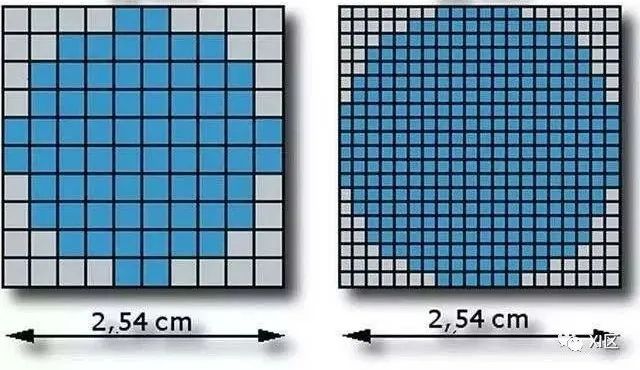

相同尺寸的圆形在相同FOV不同矩阵下呈现不同的状态(图片源自网络)

什么是各向同性呢?在容积扫描中,容积图像构成的最小单元称为体素,所谓各向同性,是指构成图像的体素呈正方体形。在X-Y平面上,体素大小由FOV和矩阵决定,如果矩阵相同,FOV越小,像素尺寸越小;如果FOV相同,矩阵越大,像素尺寸越小。

在Z方向上,体素尺寸由层厚和层中心间距决定,如果层厚与层中心间距相同,则层厚决定Z方向体素尺寸,如果层中心间距小于层厚,层中心间距越小,体素尺寸越小。因此决定各向同性的主要因素包括矩阵、FOV、层厚和层中心间距。

各向同性是指体素呈正方体形状,正方体越小,分辨率越高(图片源自网络)

我们可以简单计算一下,假设FOV为500 mm,矩阵为512x512,则X-Y方向像素尺寸为0.98 mm,此时,如果层厚也是0.98 mm,则可以达到各向同性。但是很显然,这个接近1 mm的体素大小对于追求更高空间分辨率的图像来说,有点太高了。并且,在正常体型的绝大部分人,FOV通常也不会用到500 mm。

我们现在根据实际情况重新计算一下,假设胸腹部的FOV为250-300 mm,矩阵为512x512,则X-Y平面的像素尺寸为0.49-0.59 mm,如果想要达到各向同性,需要的层厚需要保持一致,目前绝大部分CT设备的最薄层厚为0.6-0.9 mm,通过层厚已经不能实现各向同性,这时需要设置层中心间距为0.49-0.59 mm,则可以实现各向同性。如果胸腹部的矩阵为1024x1024,则像素尺寸缩小到原来的四分之一,为0.24-0.29 mm,显然如果想要实现1024矩阵时的各向同性分辨率,层中心间距需要小于0.29 mm,目前绝大部分厂家的CT设备最小层中心间距均不能实现这样的设置。因此增加矩阵在某些特定情况下仅能提高X-Y平面的空间分辨率,对于Z轴分辨率提升没有贡献。